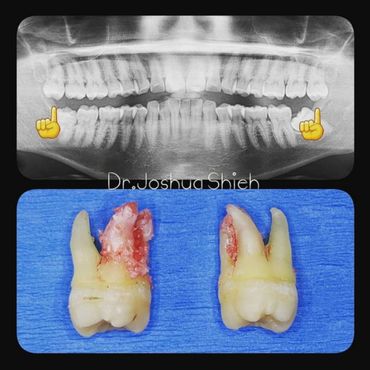

If the tooth is planned for extraction, an x-ray of the area will be taken to plan for the type of extraction.

Surgical Dental Extraction

A surgical extraction is a more complex procedure. It is used if a tooth may have broken off at the gum line or has not come into the mouth yet. Surgical extractions are commonly performed by general dentists or oral surgeons depending on the case. Sometimes it’s necessary to remove some of the bone around the tooth or to cut the tooth in half in order to extract it. For surgical extractions, patients receive local anesthetic. A suture is usually required to control bleeding and facilitate healing.